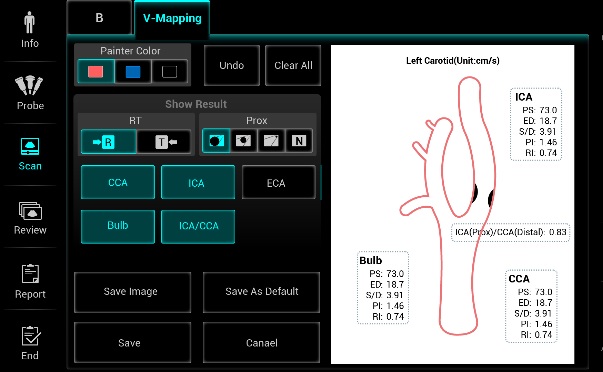

V-Mapping

Možnosť poznačenia patologického nálezu na mape cievnej anatómie.

Unikátne sledovanie cievy, optimalizácia dopplerovského okna. Nastavenie Color/Power/PW pozíciu ROI, uhol steeringu atď... Výrazné zjednodušenie vyšetrovania ciev.